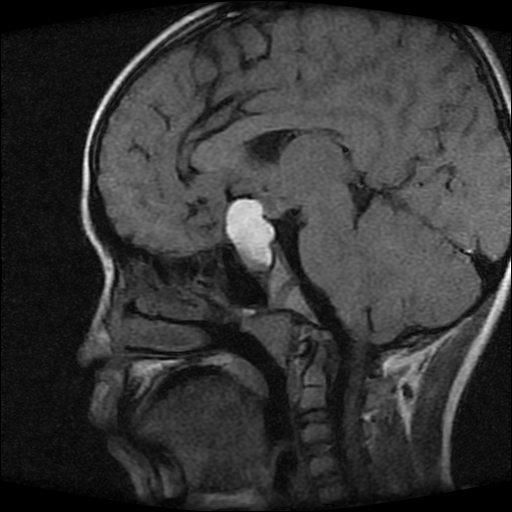

男性,12岁。反复头痛呕吐半月。脑积液无异常。病变部位ct值32hu,dwi无异常。

鞍上为主,累及鞍内,垂体受压位于鞍底。mri呈短t1、长t2信号,不太支持生殖细胞肿瘤,首考颅咽管瘤。

鞍内囊性占位性病变,t1wi、t2wi,均为高信号影。ct平扫为等密度。发病年龄较小。故首先考虑颅咽管瘤,可以做ct增强扫描